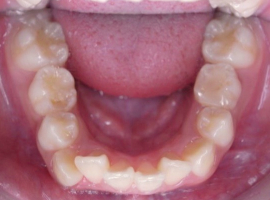

下顎

- Before